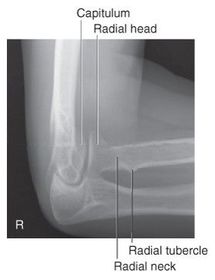

A. radial and coronoid fossas B. capitulum C. trochlea D. coronoid process E. radial tuberosity F. radial neck G. radial head H. trochlear sulcus I. trochlear notch J. olecranon process K. epicondyle L. olecranon fossa

G. superimposed epicondyles of humerus I. trochlear sulcus J. trochlear notch K. outer ridges of capitulum and trochlea L. coronoid process of ulna M. radial head N. radial neck